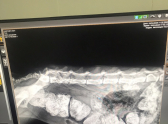

«Когда забрала Лину и сделали первый рентген, врачи были в ступоре. Не понятно, как жила эта малышка с кишечником, растянутым на весь живот. Попа в некрозе. В «Добром Докторе» провели операцию по зачистке кишечника. Прием слабительных после операции хоть как-то помогает девочке. Недержание мочи, к сожалению, исправить не получится никогда», – пишет волонтер.